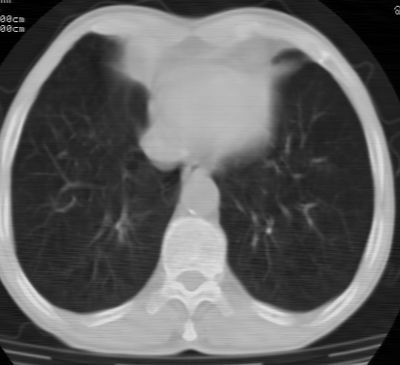

标题: CT24783:m71,既往肺心病史3年,现咳嗽,憋喘。 [打印本页]

标题: CT24783:m71,既往肺心病史3年,现咳嗽,憋喘。

1、左肺上叶spn,毛刺+分叶+血管集束征,考虑周围型肺癌可能性大

2、全小叶性肺气肿。

1)左肺上叶周围型肺癌可能。2)两肺全小叶型肺气肿。

左上周围型肺癌,全小叶型肺气肿。